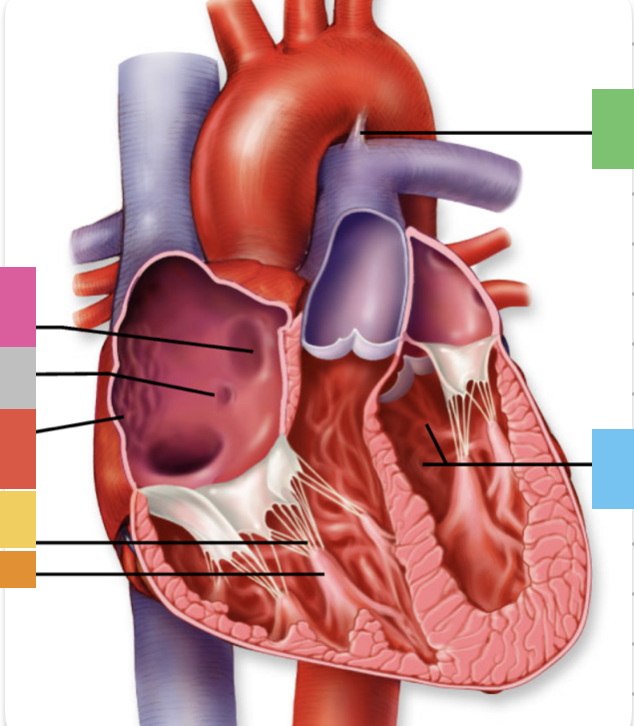

light purple

base

purple

apex

grey

right atrium

pink

right auricle

green

left atrium

green

left auricle

blue

right ventricle

orange

left ventricle

green

coronary (atrioventricular) sulcus

pink

interatrial septum

dark blue

interventricular septum

green

anterior interventricular sulcus

green

posterior interventricular sulcus

orange

aortic valve

yellow

pulmonary valve

red

tricuspid valve (right AV)

purple

bicuspid valve (left AV)

yellow

chordae tendineae

orange

papillary m.

blue

trabeculae carneae - only in ventricles

red

pectinate m. - only in R atrium

pink

fossa ovalis

grey

opening of coronary sinus